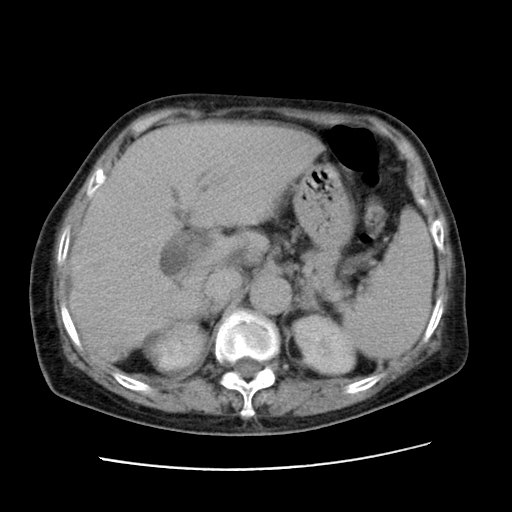

女,77.无不适

肝脏变异、异位胆囊,肝右叶肝内胆管结石并肝内胆管扩张。

肝右叶肝内胆管结石并肝内胆管扩张。

肝右叶肝内胆管结石并肝内胆管扩张

胆总管扩张

肝右叶肝内胆管结石并肝内胆管扩张。胆总管下段梗阻,考虑壶腹部占位。

右侧肝内胆管局限性扩张,其内密度不均匀,扩张的胆管壁增厚,考虑肝内胆管炎合并结石可能性大

肝右叶肝内胆管结石并肝内胆管扩张。胆总管下段梗阻,考虑壶腹部占位。支持